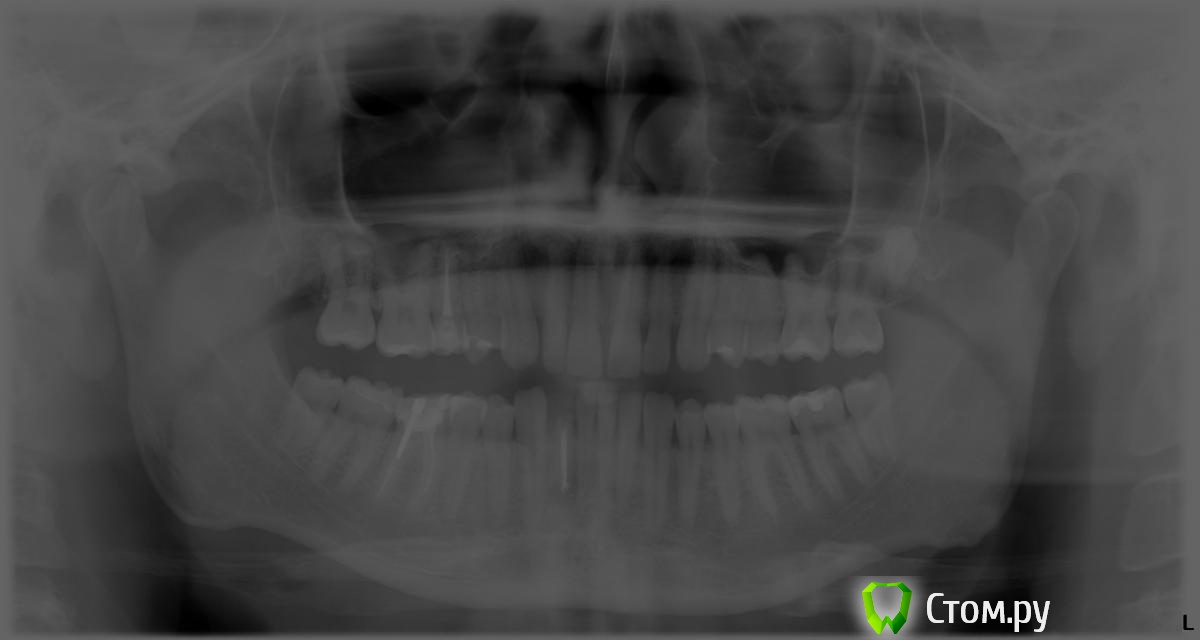

Александр83 Опубликовано 14 октября, 2014 Автор Поделиться Опубликовано 14 октября, 2014 Дополнительный снимок по всем зубам. Ссылка на комментарий

red_butler Опубликовано 14 октября, 2014 Поделиться Опубликовано 14 октября, 2014 Как давно проведено лечение корневого канала? Ссылка на комментарий

Александр83 Опубликовано 14 октября, 2014 Автор Поделиться Опубликовано 14 октября, 2014 Как давно проведено лечение корневого канала?6лет назад. Ссылка на комментарий

red_butler Опубликовано 14 октября, 2014 Поделиться Опубликовано 14 октября, 2014 Я бы удалил 1 Ссылка на комментарий

Гарриевич Опубликовано 14 октября, 2014 Поделиться Опубликовано 14 октября, 2014 если кто и возьмется перелечивать, я не думаю что даст гарантию.если бы я этот зуб изначально лечил и через 6 лет получил такой результат, то однозначно удалил бы Ссылка на комментарий

Korel Опубликовано 14 октября, 2014 Поделиться Опубликовано 14 октября, 2014 Удаляйте без сожалений. Ссылка на комментарий

faity Опубликовано 14 октября, 2014 Поделиться Опубликовано 14 октября, 2014 плюсую. можете конечно и полечить, если у вас много ненужных денег и времени, но я бы не стал http://s017.radikal.ru/i426/1410/4a/31aaf8c57b2c.jpg Ссылка на комментарий

Гарриевич Опубликовано 15 октября, 2014 Поделиться Опубликовано 15 октября, 2014 Тут два варианта:1) после лечения вы прождете около полугода-год времени для наблюления за зубом1а) результат будет и зуб покроют коронкой1б) результата не будет и зуб удалят2) в процессе перелечивания возникнут осложнения и зуб удалят Ссылка на комментарий